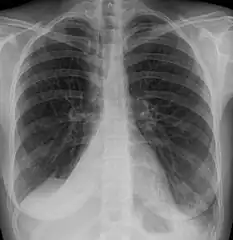

Atelectasis of a person's right lung

Atelectasis is the collapse or closure of a lung resulting in reduced or absent gas exchange. It is usually unilateral, affecting part or all of one lung.[2] It is a condition where the alveoli are deflated down to little or no volume, as distinct from pulmonary consolidation, in which they are filled with liquid. It is often called a collapsed lung, although that term may also refer to pneumothorax.[1]

Clinically significant atelectasis is generally visible on chest X-ray; findings can include lung opacification and/or loss of lung volume. Post-surgical atelectasis will be bibasal in pattern. Chest CT or bronchoscopy may be necessary if the cause of atelectasis is not clinically apparent. Direct signs of atelectasis include displacement of interlobar fissures and mobile structures within the thorax, overinflation of the unaffected ipsilateral lobe or contralateral lung, and opacification of the collapsed lobe. In addition to clinically significant findings on chest X-rays, patients may present with indirect signs and symptoms such as elevation of the diaphragm, shifting of the trachea, heart and mediastinum; displacement of the hilus and shifting granulomas.[10]